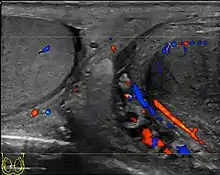

- Blood – ESR high

- Urine – Cultural & Sensitivity test

- Ultrasound scanning